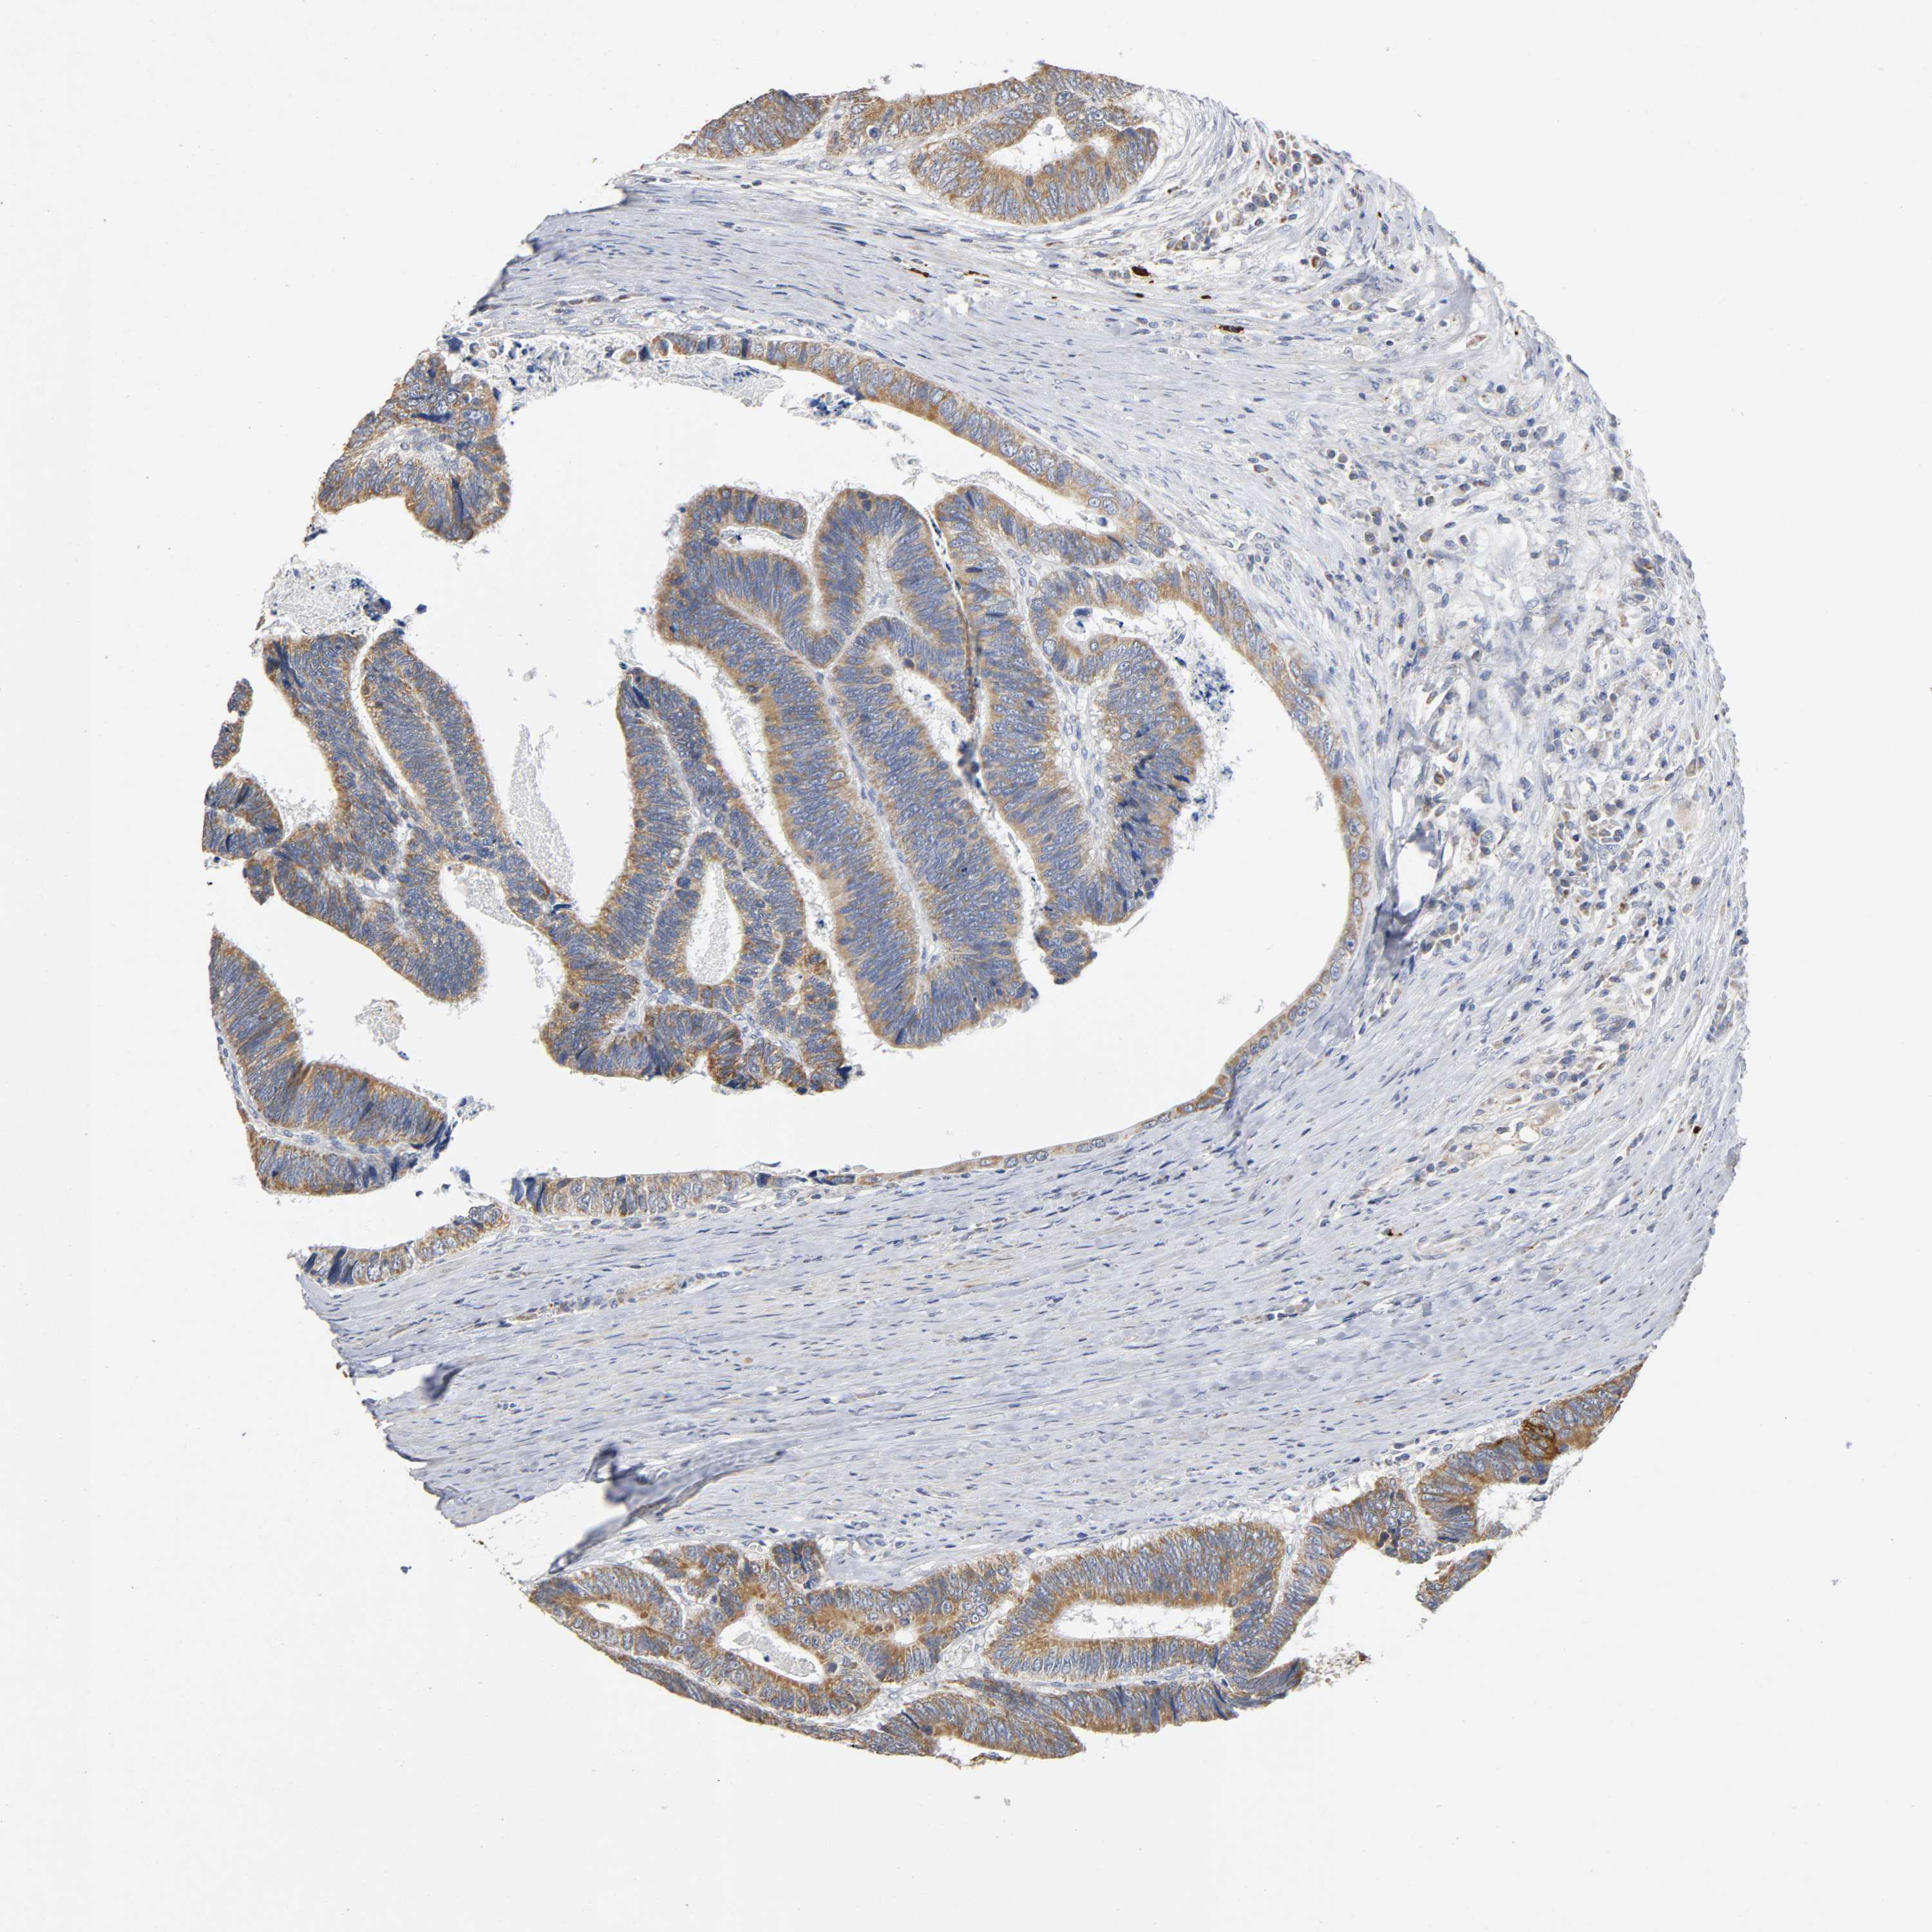

CANCER COLORECTAL CANCER Show tissue menu

Colorectal cancer

Human cancer

Colon adenocarcinoma